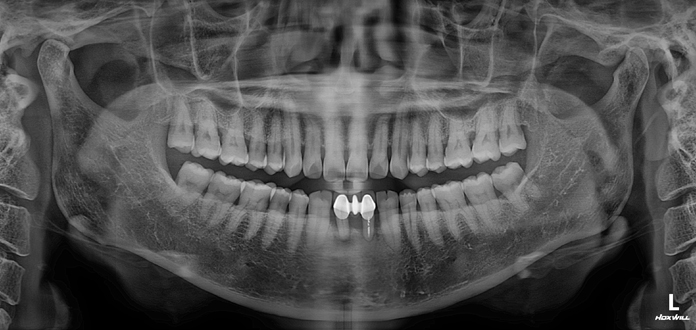

• Before

After